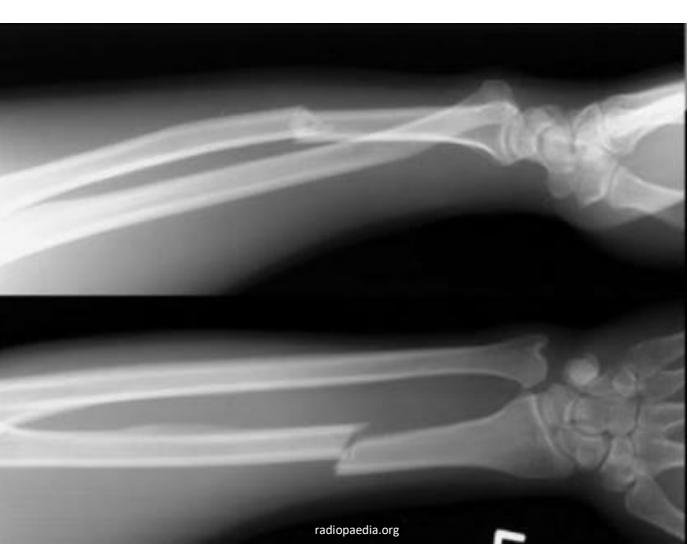

Galeazzi Fracture

-

Treatment: Surgery -

Monteggia Fracture

- Location: Proximal ulna fracture w/ radial head dislocation ย fracture of the proximal (or midโshaft) ulna with dislocation of the radial head at the elbow. ย